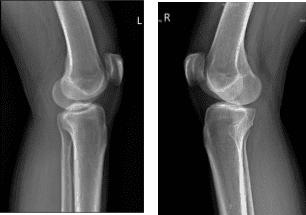

She presented X-ray which showed no fracture or post fracture deformity. Preserved joint spaces. No osteophytes or erosions. Unremarkable soft tissue structures for both knees.

X-ray Bilateral Knees 3 views each